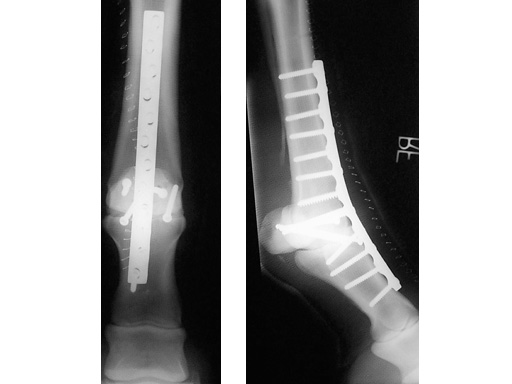

5.5 mm Broad LC-DCP

The use of the 5.5 mm Broad LC-DCP is indicated in treating equine long bone fractures. The plate features the limited contactdynamic compression plate designand is made of stainless steel. It is 5.7 mm thick, 16 mm wide, and available in lengths from 178 mm (10 holes) up to 322 mm (18 holes). The existing 5.5 mm Cortex Screws can be used with this plate.

The significantly increased stiffness in the LC-DCP construct should result in less micromotion at the arthrodesis site and therefore less cyclic fatigue and delayed fusion. The design affords a more uniform cross section that should reduce stress concentration at the screw holes.

Case 1: 3-year-old thouroughbred.

The arthrodesis was necessary, because the animal suffered a breakdown injury during a race.